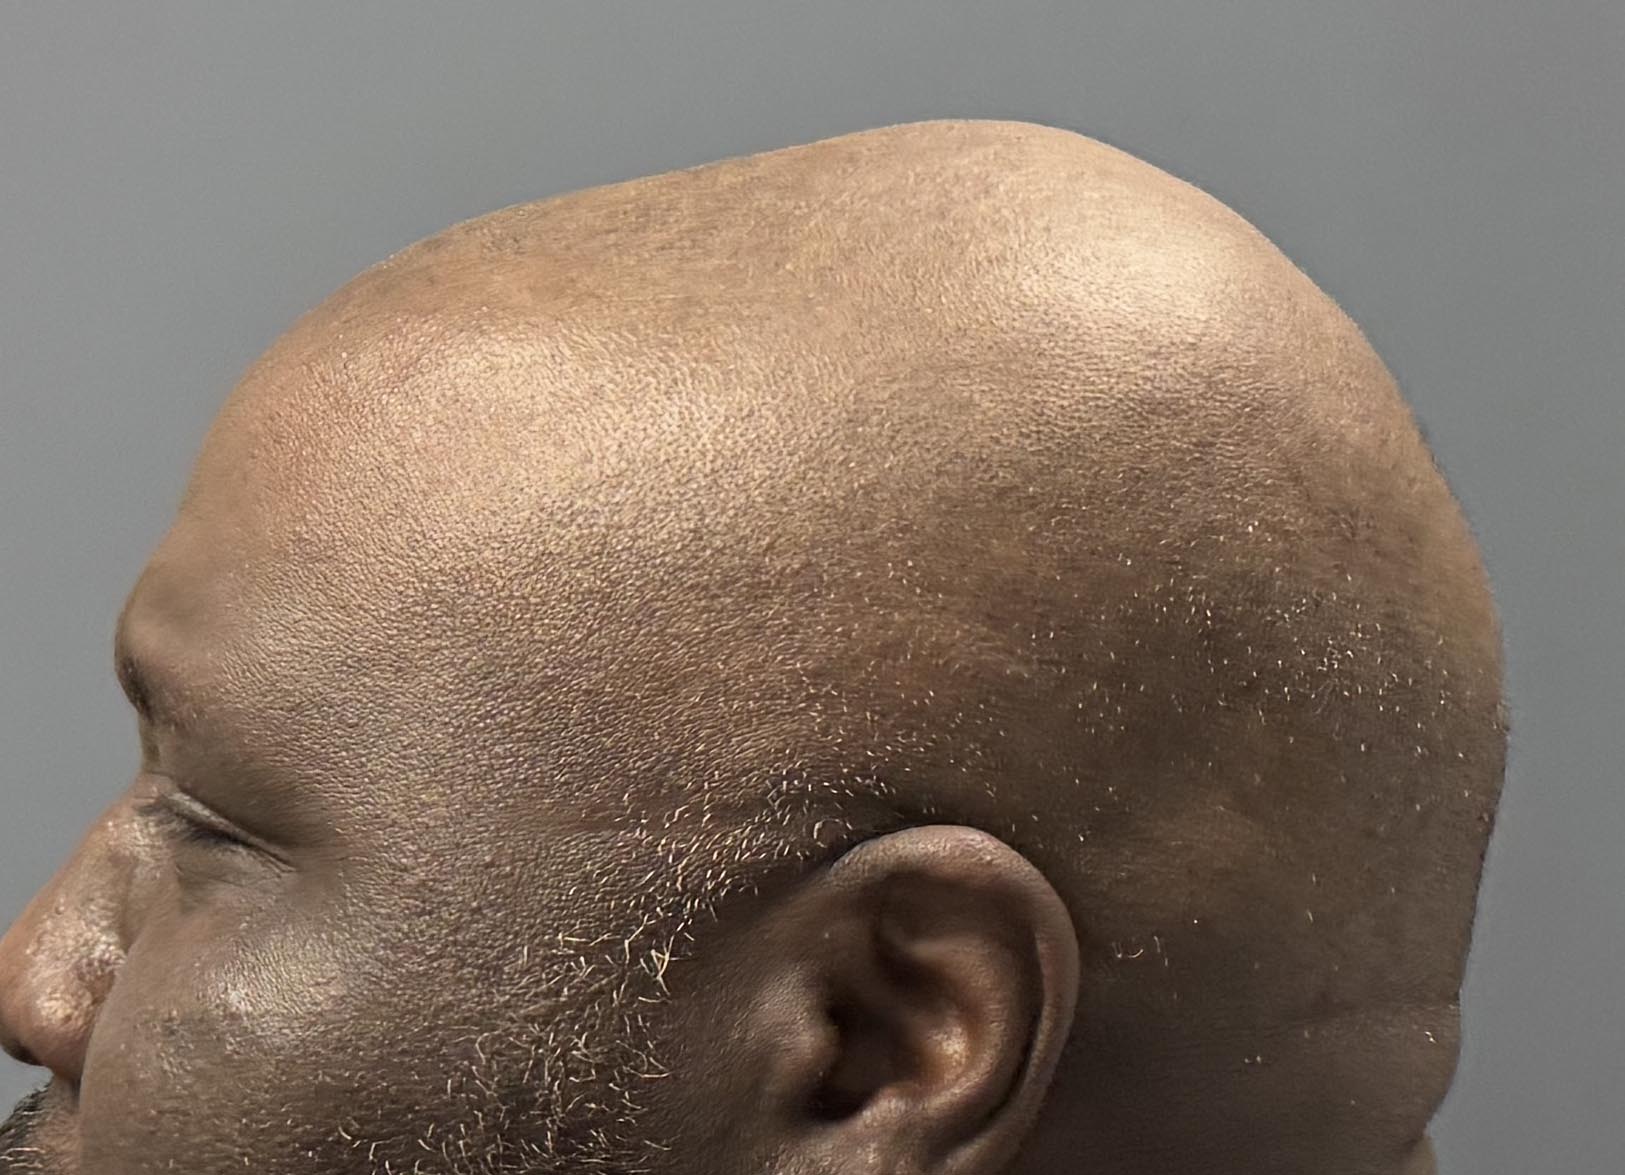

Patient 100

Desire for reshaping of an asymmetric flat back of the head in a shaved head male.

A combined back of the head reshaping procedure was done with a custom skull implant, sagittal ridge reduction and a right temporal muscle reduction.

Desire for reshaping of an asymmetric flat back of the head in a shaved head male.

A combined back of the head reshaping procedure was done with a custom skull implant, sagittal ridge reduction and a right temporal muscle reduction.